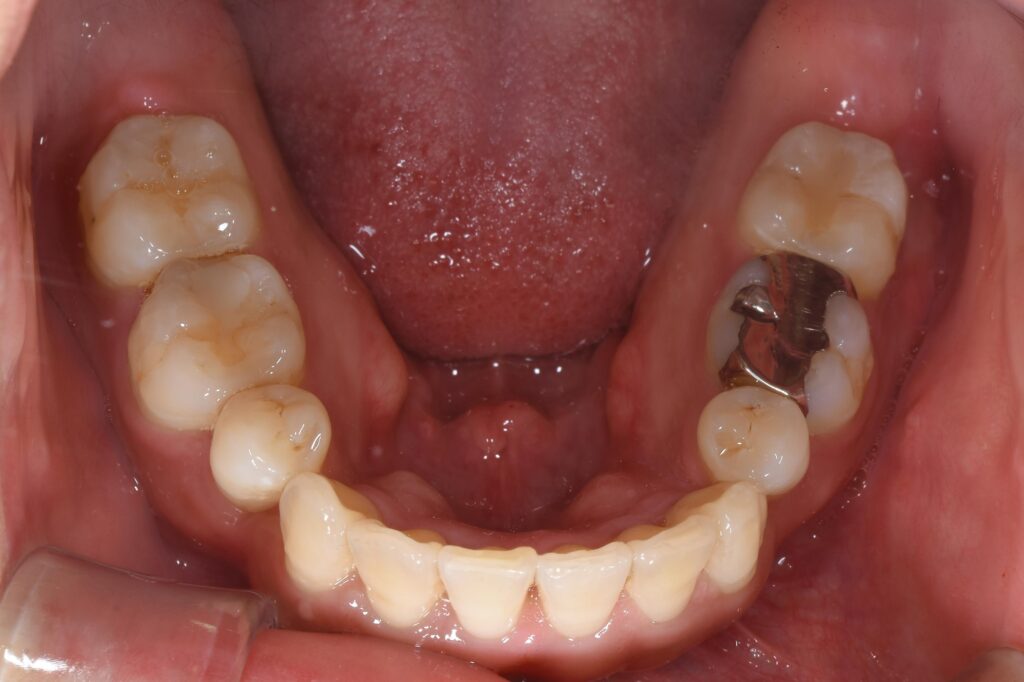

【矯正開始1年後】

いかがでしょうか。

患者様の歯並びがきれいになったと喜んで頂けました(^^♪